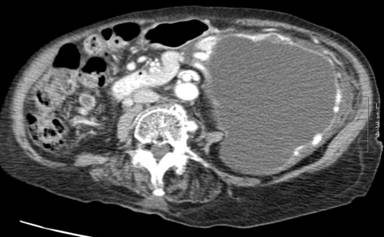

Madam WFE, a 92-year-old Chinese female presented in March 2013 with a three month history of upper abdominal discomfort, early satiety and weight loss of 7 kg. Her past medical history includes hypertension and a previous transient ischemic attack but there was no history suggestive of acute or chronic pancreatitis. Abdominal examination revealed a vague, non-tender epigastric mass with moderate abdominal distension. Her blood parameters and tumor markers were normal. CT scan of the abdomen showed a large cystic lesion in the tail of pancreas with no obvious communication with the main pancreatic duct and no features of malignancy (Figure 1). Esophagogastroduodenoscopy (EGD) revealed normal gastric mucosa with a significant bulge at the posterior wall of the gastric antrum. She was diagnosed as having a pancreatic cystic neoplasm (PCN) with partial gastric outlet obstruction (GOO). In view of her age and co-morbidities, she was planned for an EUS-guided pancreatic cystic neoplasm (EUS-PCN) drainage as palliation for the GOO. However, it was felt that the standard pseudocyst drainage technique of using multiple plastic stents was unlikely to be of benefit as the fluid collection would re-accumulate as long as the tumor remained. Therefore, the decision was made to insert a covered self-expandable metal stent (CSEMS) with an anti-migration system.

Figure 1. Large cystic tumour arising from tail of pancreas. |